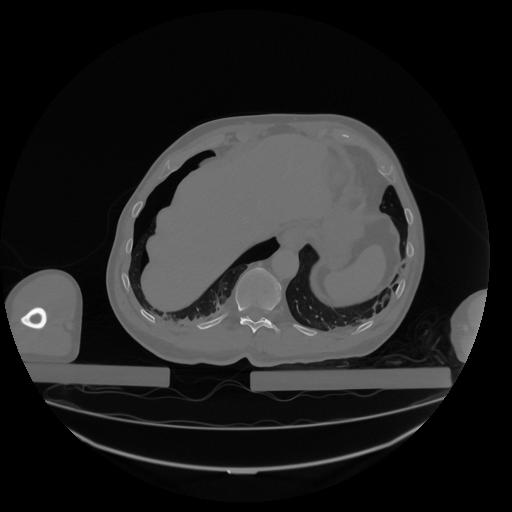

34 CUERPO,CE,Vol,1.0,CUERPO,,